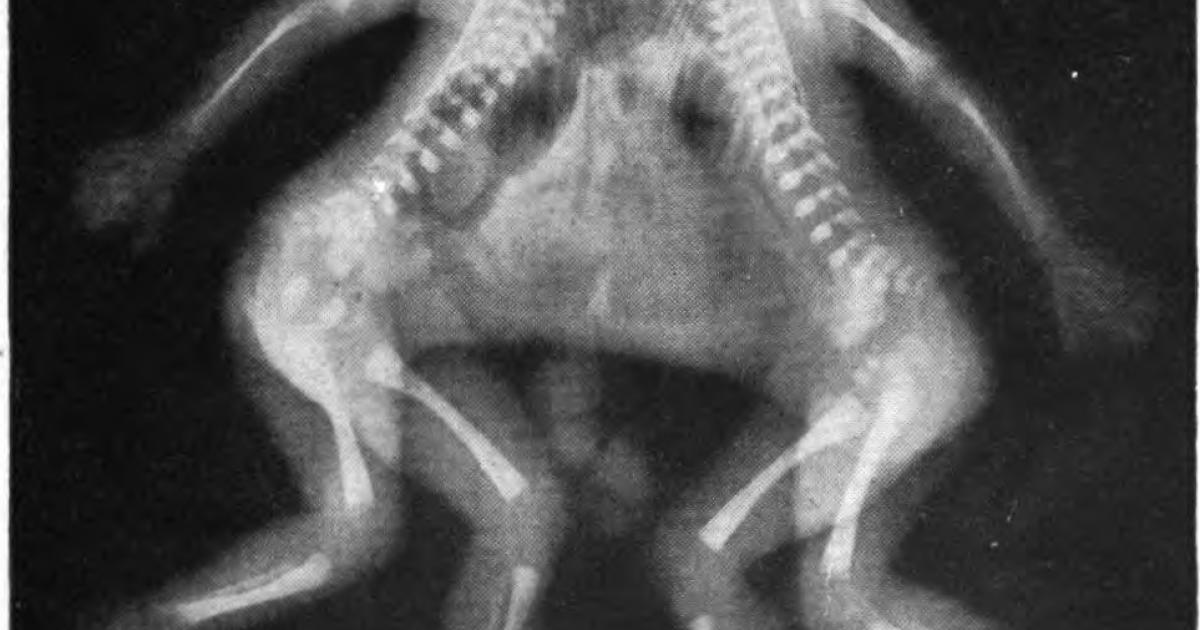

The photo accompanying this piece at the top of the article is not from the case discussed. As you can tell in the x-ray picture of conjoined twins there are fundamental differences, for one, there are four legs.